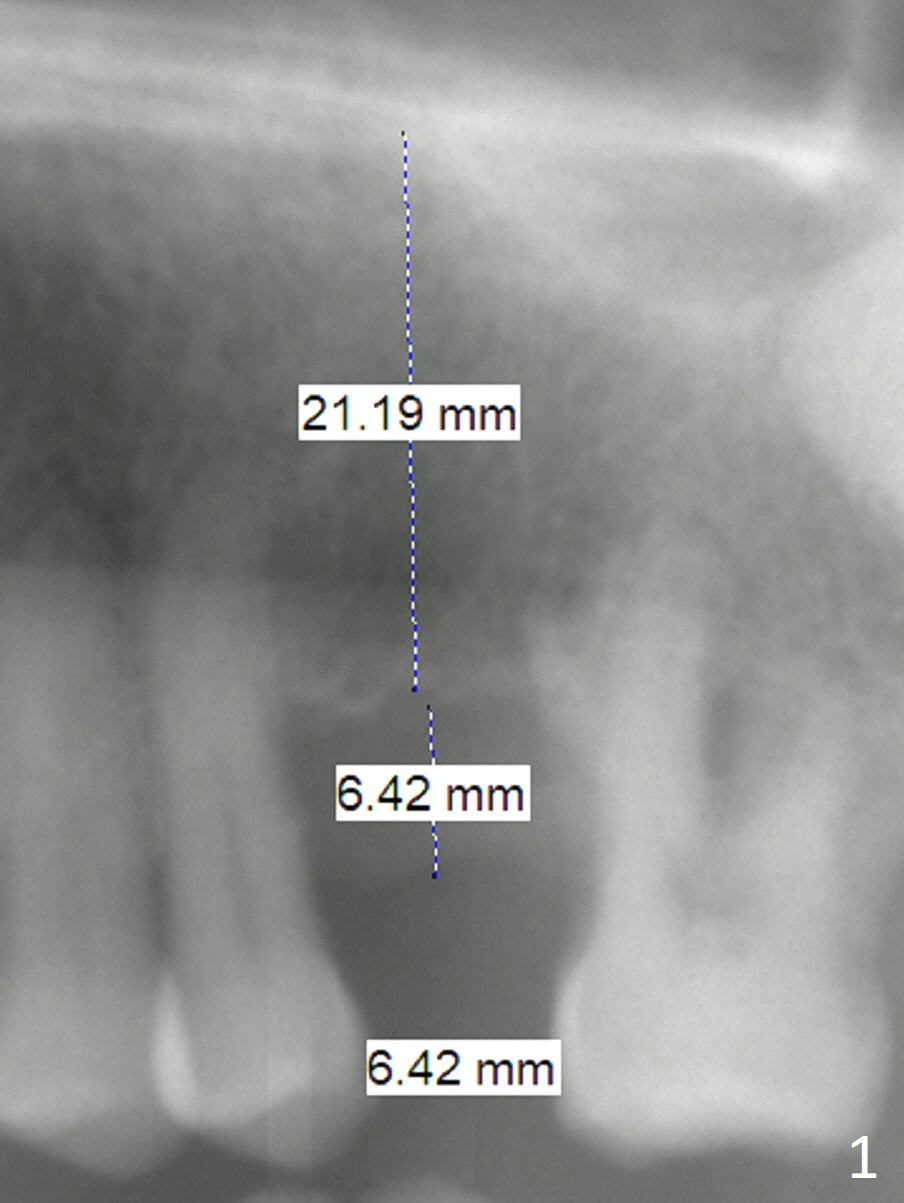

A 54-year-old man will return for #14 implant placement approximately 4 months post #3 one (Fig.1).  The mesiodistal space is narrow; the diameter of the implant and abutment will be 3.8-4.5 mm.  The gingiva is thick; the cuff of the abutment should be 5 mm or a milled abutment will be used.  The vertical dimension is also large; the abutment length will be 7 mm or use a milled abutment.